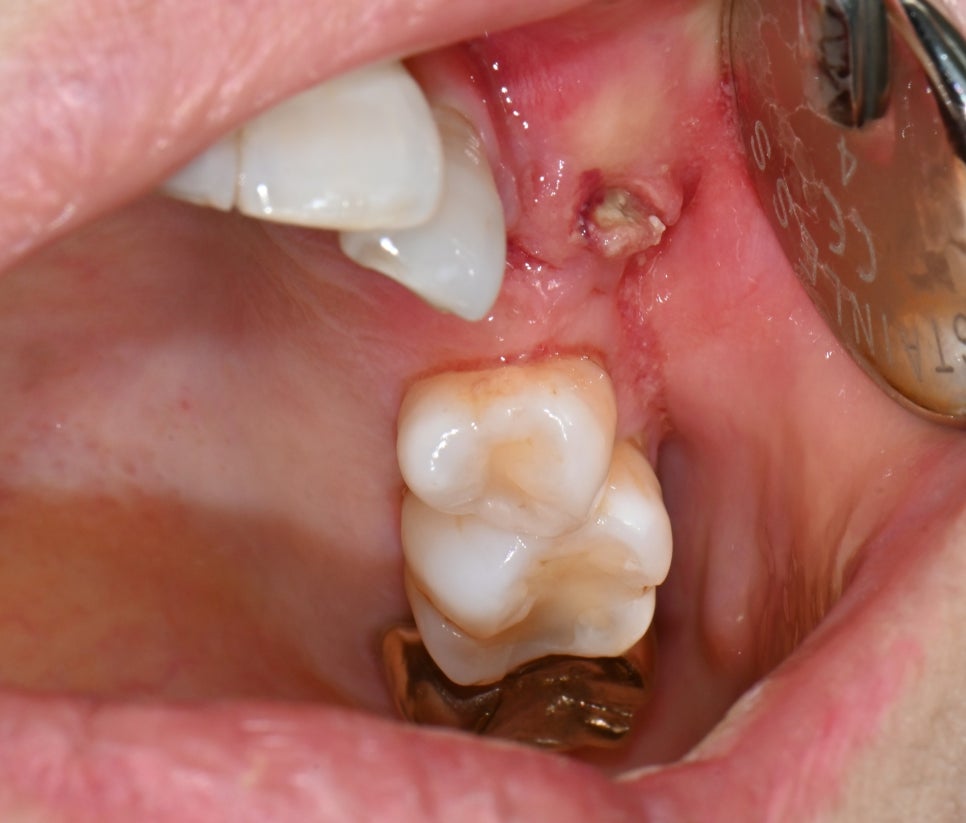

📸

This photo was taken in more detail. When examined visually, there was a mass of pus inside the gum,

and the diagnosis was osteomyelitis.

In other words, the inflammation was not just on the surface; it had spread into the bone.

Initial oral photo of the osteomyelitis patient